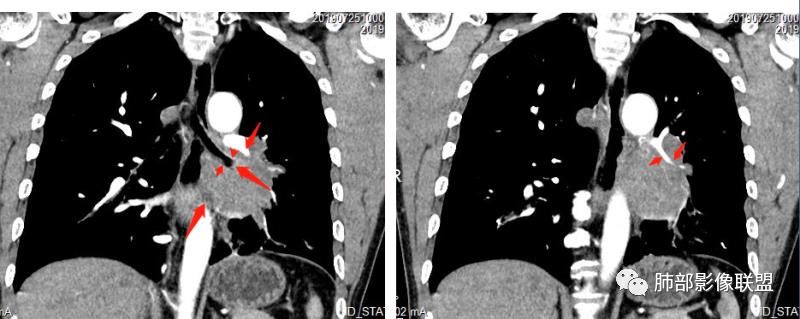

1.左下肺门区巨大肿块,支气管显示不清,轻度阻塞性炎症,没有明显肺不张,提示管腔受压狭窄可能性大于堵塞,这较少见于鳞癌。

2.病灶边缘光滑,未见明显分叶、毛刺,未见明显强化,这符合腺癌影像学特点,却符合神经内分泌癌表现。

3.病灶内密度均匀,轻到中度均匀强化,大病灶未见明显液化坏死区及空洞,不符合鳞癌而符合小细胞肺癌特点。

4.病灶内有肺动脉走形,血管局部受压,未见破坏,病灶乏血供,呈血管包埋或血管造影征;侵袭性力强及破坏力弱、血管漂浮都符合SCLC,所以鳞癌的可能性也不大。

5.左肺门块影或淋巴结肿大,竭力挤兑肺门血管结构,呈冰冻肺门;有时候SCLC可以单独呈现冰冻肺门,而没有没有冰冻纵隔。